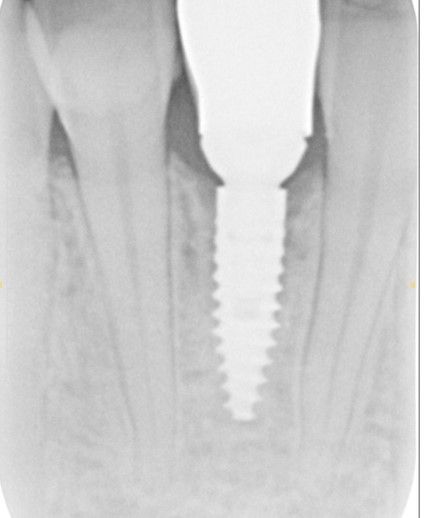

Case 1 - Upper incisor and bone loss due to root fracture after trauma to the tooth. Replaced with dental implant and simultaneous bone grafting